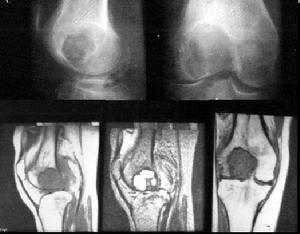

組織細胞纖維瘤有典型的X線特徵有些學者認為不需經組織學檢查,就能對大多數病例作出正確診斷。病變始於長骨的乾骺端,靠近骺板,且總在一側皮質上膨脹、偏心性隨骨的生長發育病變可以逐漸向骨幹移行,病灶內為界限清楚透亮陰影,呈分葉狀卵圓形,周邊有一硬化緣。病變縱軸與長骨一致,病變小自1cm,最大可達15cm。病變發展有侵入髓腔、破壞整個乾骺端導致整個皮質變薄,造成病理性骨折。病變可隨骺板生長而擴大骺閉合後病變有可能停止生長

多發組織細胞纖維瘤影像學也有典型特徵性表現,可在同一骨內有多個病灶,也可不在同一骨。病灶之間不連續。單個病變與單發相似。多表現侵入髓腔,病變起始也在乾骺端,進一步發展向骨幹移行病變常常對稱性存在,這種情況在上肢更為常見,組織細胞纖維瘤導致骨折在下肢病變中更常見。